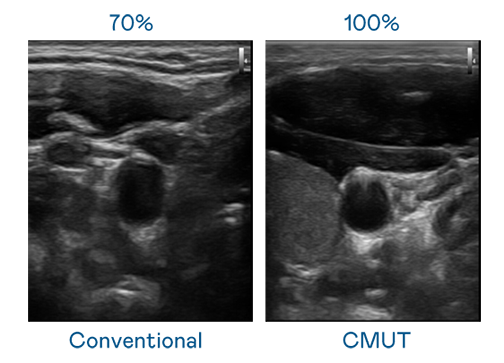

CMUT 技术是一种用电容式微机电元件来产生超音波讯号的技术。与传统 PZT 压电式技术相比,CMUT 频宽增加 30%,更宽频的超音波讯号让影像解析度大幅提升,是实现高影像品质医疗超音波扫描、促进精准医疗发展的关键技术。

超音波影像的解析度高低,首先取决于探头能发出的讯号频宽。羞羞视频18 CMUT 可提供高清晰的超音波讯号,提供高频宽、高灵敏度、影像纹理细节更高的超音波影像,协助医护人员缩短影像判读时间及利用精准的医疗影像进行诊断。